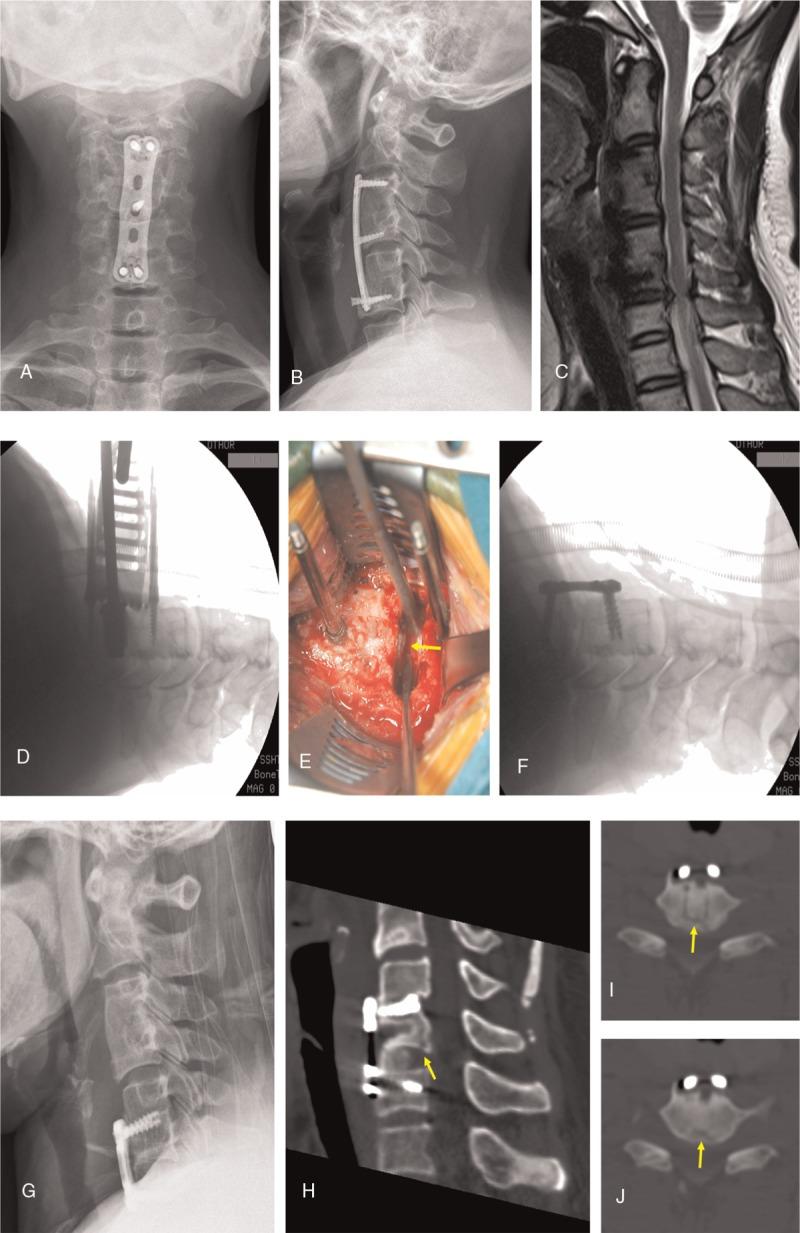

The patient had received discectomy and fusion procedure on C3/4 and C5/6 to relieve her radicular pain nearly 4 years prior. Neurologic examination revealed a diminished sensation at the C6-C8 skin areas and level Grade-4 power in the left wrist extensor and grip muscle strength. Magnetic resonance imaging (MRI) showed disc herniation compressing the spinal cord at C6/7. Computed tomography (CT) scans showed intervertebral fusion in both the C3/4 and C5/6 segments.

Surgery was performed to remove the plate and replace C6/7 with an artificial disc, but a transverse cleavage endplate cortical fracture was detected after cutting the blades. Thus, we terminated artificial cervical disc replacement intraoperatively and changed to discectomy and fusion in C6/7.

The patient's symptoms were remarkably relieved. Postoperative CT scans showed a transverse cleavage fracture in the backside of the C6 caudal endplate. Good fusion was achieved after 6 months.